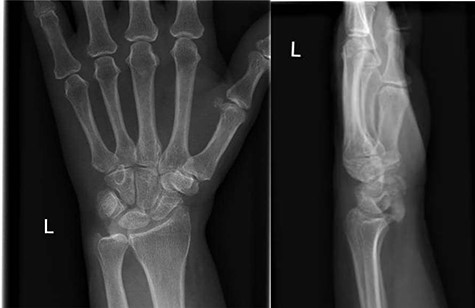

In this case a 57-year-old female patient with a past medical history of degenerative spondylosis presented to the emergency department with a 1-week history of left wrist pain. There was no history of antecedent trauma. The patient was constitutionally well, with the wrist being globally tender with a limited range of motion. There was palpable firm swelling over the volar aspect of the wrist with no overlying skin changes. Neurovascular examination was normal. Bloods taken on presentation revealed a normal white cell count, serum urate and C-reactive protein. Initial radiographs showed marked, poorly defined soft tissue calcification overlying the palmar aspect of the lunate with no associated bony injury (Fig. 1).

AP and lateral radiographs of the left wrist on initial presentation to the emergency department, showing amorphous calcification overlying the lunate.